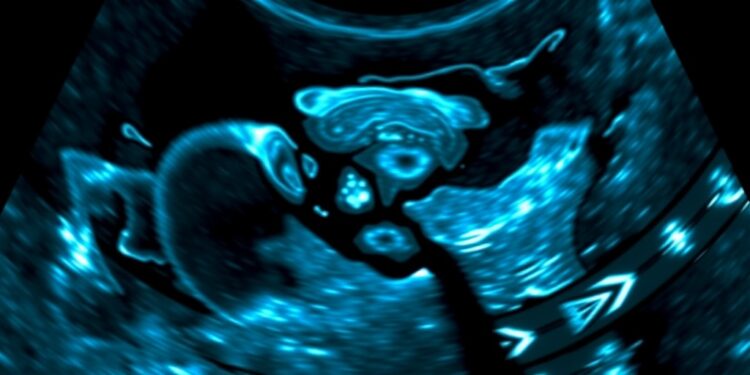

At the forefront of this discussion is the work of Professor Zhou and his distinguished team, who have developed CoLDiT, a groundbreaking conditional latent diffusion model. This model harnesses the power of a diffusion transformer (DiT) backbone to generate highly realistic breast ultrasound images, conditioned specifically on Breast Imaging-Reporting and Data System (BI-RADS) categories. This innovation represents a significant step towards overcoming the data-sharing barriers that have long hindered medical research.

The CoLDiT model was trained on an extensive and diverse dataset, comprising 9,705 breast ultrasound images sourced from 5,243 patients across 202 hospitals. By incorporating images obtained from various ultrasound vendors, the team ensured a comprehensive representation of the variations inherent in real-world breast ultrasound imaging. This multidimensional approach not only enhances the diversity of the dataset but also fosters the generation of more realistic synthetic images.

This pioneering research stands out for several reasons. First, the utilization of a vast, multicenter dataset encompassing diverse sources fosters the ability to capture a wide array of variations found in real breast ultrasound images. This comprehensive approach leads to the creation of synthetic images that are not only visually realistic but also clinically relevant, thus enhancing their applicability in medical contexts.

Second, the decision to employ a pure transformer backbone rather than traditional U-Net architectures leverages the transformers’ innate capabilities in capturing long-range dependencies. This critical technological choice enables CoLDiT to produce images that are more coherent and detailed compared to previous models, thus pushing the boundaries of what synthetic data can achieve.

Moreover, the conditioning of image synthesis on BI-RADS labels represents a significant advancement in medical imaging. By generating ultrasound images that align closely with specific BI-RADS categories, the CoLDiT model enables tailored image synthesis for various clinical scenarios. This functionality is essential for accurate diagnosis and treatment planning, offering a powerful tool for radiologists and clinicians alike.